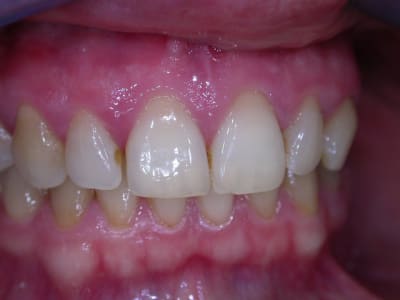

examen buccal .........voir les photos ........après ........ca vient

Bon controle de plaque, pas de tartre ni de colorations, inflammation en palatin seulement...